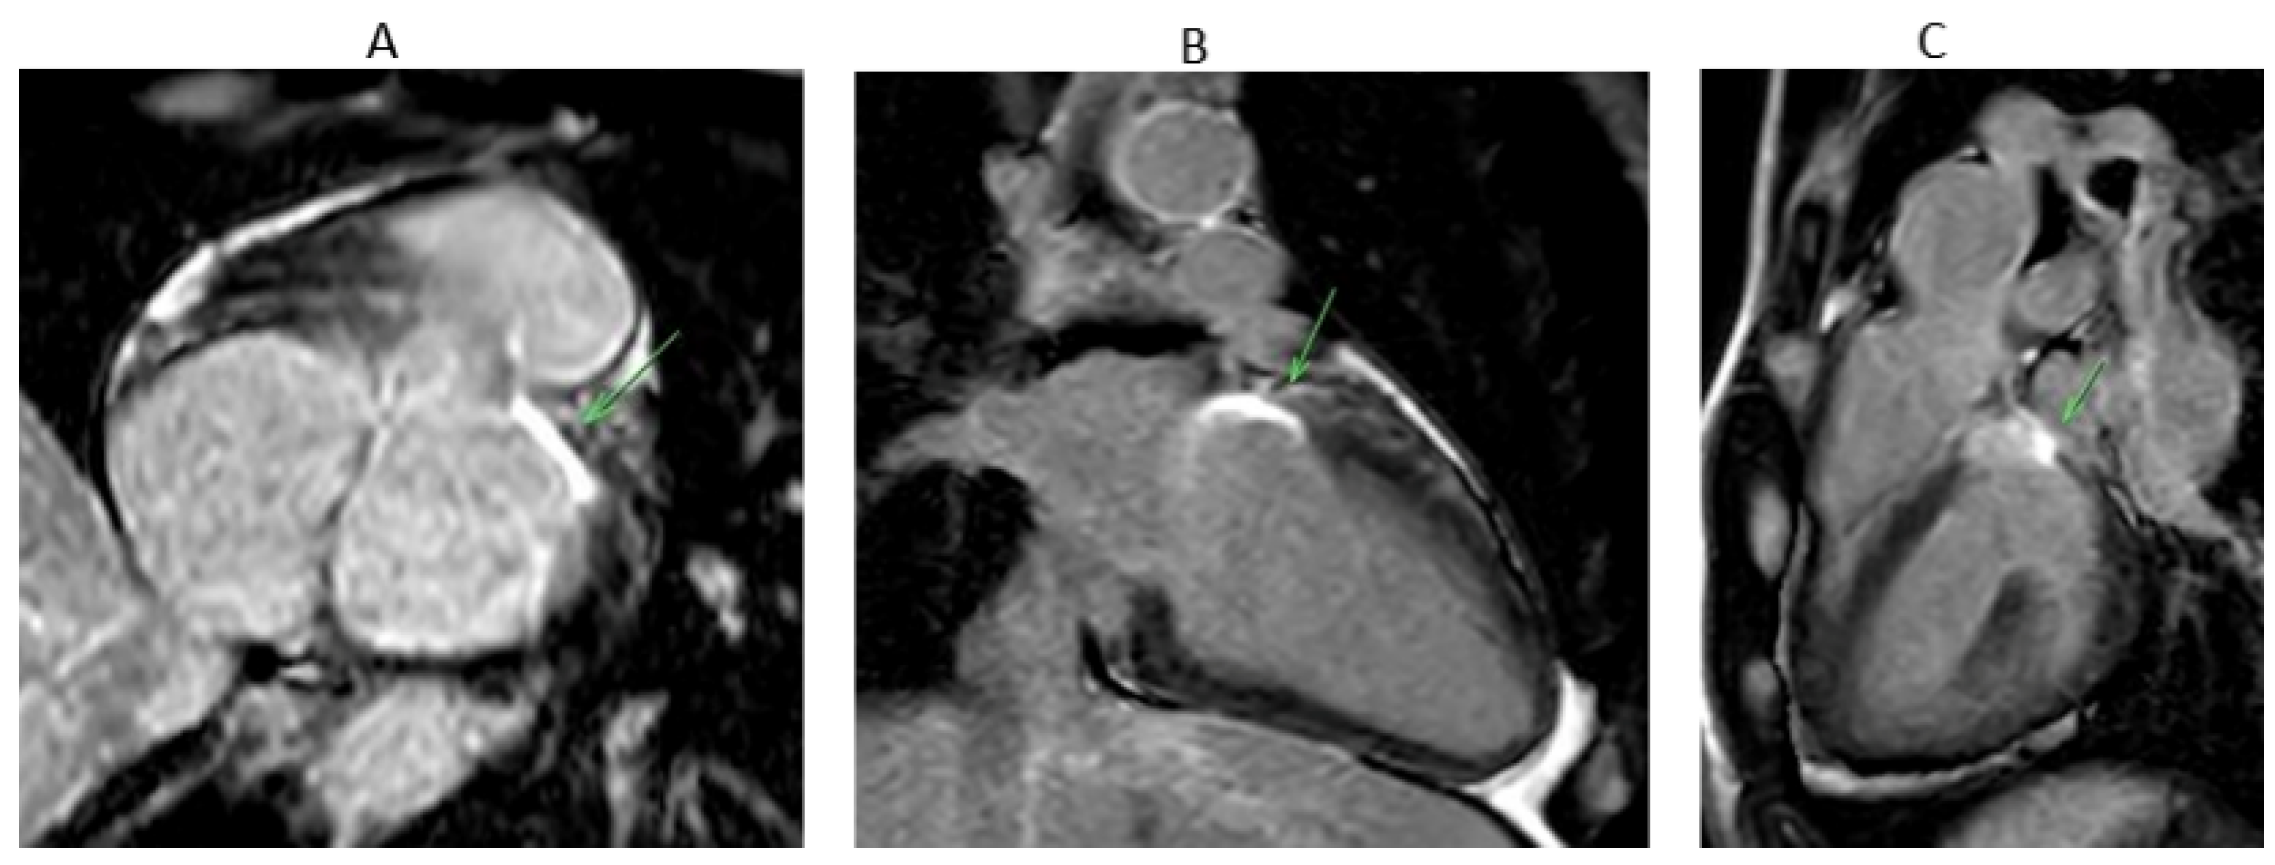

7.1. Procedure

8.2. Ablation Sites